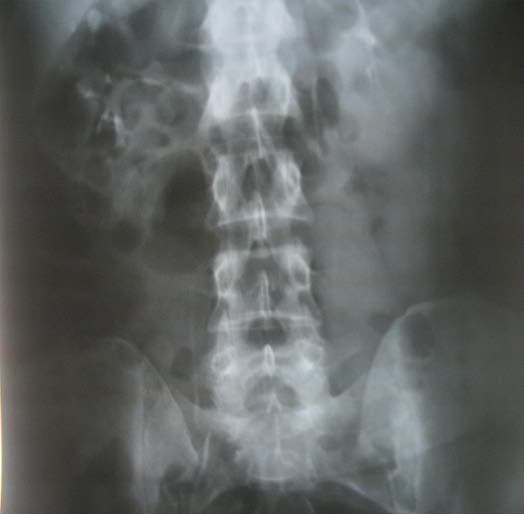

We are going to present the case of a female patient referred to our clinic with the initial ultrasound Author ? ? ? ?: Urology Department, Regional Hospital -Gjilan, UHC "Mother Theresa" Tirana, Albania, SLK Kliniken, Internal Medicine, Heilbronn, Germany. e-mail: [email protected] diagnosis of right giant renal cyst about 10 cm. Physical examination revealed no abnormalities. Given the result of the ultrasound (thick walls and small irregularities) and the possibility of a complicated cyst, we decided to investigate the matter further, and programmed the patient for an enhanced abdominal computer tomography with intravenous contrast.

The enhanced CT images revealed a right kidney cystic mass, with a 10 cm diameter, thick irregular walls with contrast enhancement, hyperdens content, and no pathological lymph nodes or distant metastases. The diagnosis was a Bosniak IV.